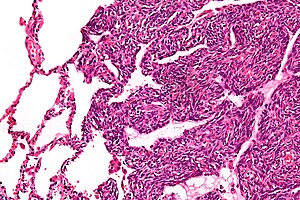

Micrograph of a monophasic synovial sarcoma. The histologic appearance is non-specific and overlaps with MPNST and fibrosarcoma. H&E stain.

Two cell types can be seen microscopically in synovial sarcoma. One fibrous type, known as a spindle or sarcomatous cell, is relatively small and uniform, and found in sheets. The other is epithelial in appearance. Classical synovial sarcoma has a biphasic appearance with both types present. Synovial sarcoma can also appear to be poorly differentiated or to be monophasic fibrous, consisting only of sheets of spindle cells. Some authorities[3] state that, extremely rarely, there can be a monophasic epithelial form which causes difficulty in differential diagnosis. Depending on the site, there is similarity to biphenotypic sinonasal sarcoma, although the genetic findings are distinctive.